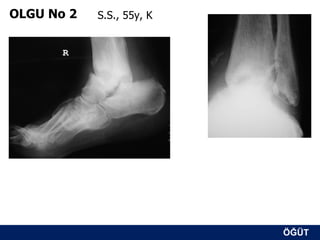

OLGU No 2   S.S., 55y, K

ÖĞÜT

Erken postop